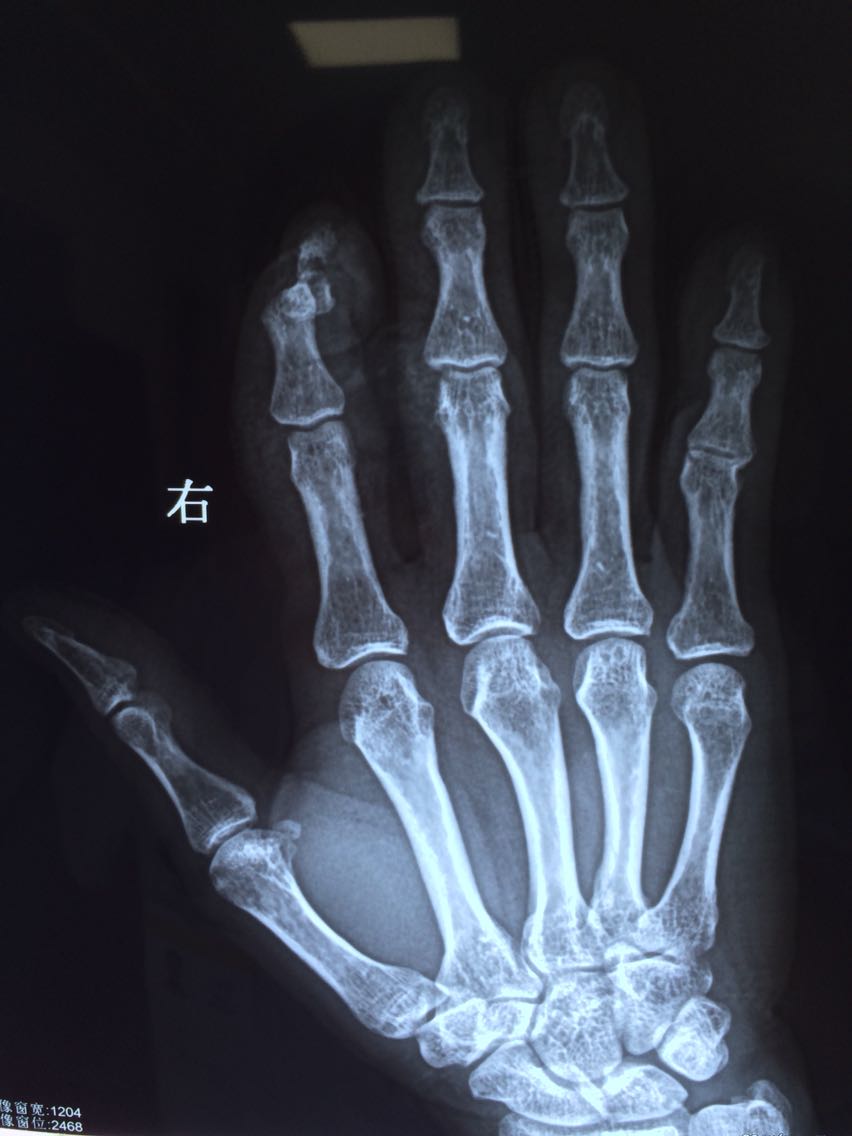

电锯割伤右手示指致流血疼痛活动受限2小时。患者2小时前不慎被电锯割伤右手示指,当即感伤处疼痛,流血不止,院外简单包扎后急来院。

查体:右手示指屈曲畸形,可见自中节桡侧致远节尺侧长约4cm斜行伤口,中度污染,流血不止,可见骨折断端,末端血运可,感觉麻木,余手指未见异常。

诊断:开放性指骨骨折 治疗:急诊行创面清创缝合、血管神经探查、指骨骨折复位钢针固定术